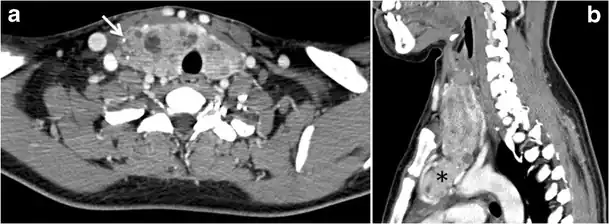

Fig. 4. A 45-year-old male patient presented with anterior mediastinal metastatic PTC lesions and occult primary on imaging. Histopathology examination of the resected thyroid gland revealed micro-foci of PTC; the largest, in the isthmus, measured 4 mm. a transverse greyscale ultrasound of the thyroid demonstrates homogeneous gland with normal echogenicity and size. No focal lesion or micro-calcifications. b Non-enhanced CT scan obtained as part of PET/CT examination shows a heterogeneous, large, relatively dense anterior mediastinal mass (white arrow) with peripheral calcification (arrowheads). Thyroid gland has normal CT appearance with no abnormal FDG uptake (not shown).[1] -

Fig. 13. A 27-year-old female patient known to have goiter. a, b Axial and sagittal enhanced CT scan images of the neck demonstrate a heterogeneously enhancing, enlarged thyroid gland with scattered calcifications (white arrow), cystic changes, and substantial retro-sternal extension (black asterisks). No lymphadenopathy or substantial airway narrowing.[1] -